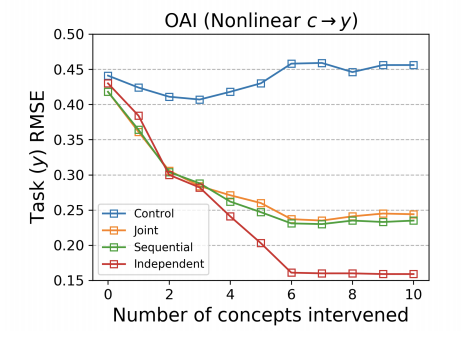

Figure 1 indicates that, since the intervenability of the joint and sequential CBMs is inferior to that of the independent CBM as per Koh et al. (2020), the concept may not be used as intended. This is likely an artifact of one-hot encoding each concept values. We suggest that future work studies how the success of intervenability varies for different concept representations: binary, scalar, one-hot encoded categoricals, etc.

Table 1 demonstrates that the performance of the joint CBM far exceeds that of the concept oracle, as the joint achieves much lower error. This suggests that the joint CBM is learning useful information for predicting the target beyond simply getting the concept correct, that is, there is no concept bottleneck. Note that the joint CBM will be sensitive to the choice of ; however, we use the same as Koh et al. (2020) in our experiments. In contrast, the independent and sequential CBMs have no incentive to learn the targets before the concept layer, and thus achieve similar predictive performance to the concept oracle. On reflection, this is not surprising: each concept is represented as a scalar at the concept layer, but is often categorical or binary in the real-world. Thus, extra information about the targets is likely learned in the joint CBM. When all concepts are used (rightmost column of Table 1), the concept oracle achieves low error, suggesting that all 10 concepts together capture the target well. However, it may be difficult to obtain a full set of concepts that well specify the target.